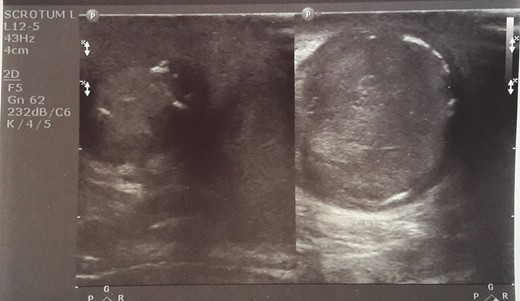

Initial sonographic findings were suggestive of epididymo-orchitis. The testis was well perfused and in normal position (Fig. 1). He was admitted for 3 days to start intravenous anti-inflammatory and antibiotic treatment and discharged under antibiotic treatment. Re-examinations were scheduled to assess treatment. On first reexamination, a week later, edema had subsided and the testis appeared hard, indurated and painless (Fig. 2). Ultrasound was still suggestive of epididymo-orchitis. Nevertheless suspicion for a testicular tumor was raised because of persistence of clinical and sonographic findings. An earlier appointment was scheduled this time. Five days later, at the second reexamination, another ultrasound showed reduced testicular perfusion that reached only the periphery of the testicular parenchyma (Fig. 3). The boy was operated as an emergency. Intraoperatively testis was non-twisted, with normal vas and vessels that ended in a necrotic testicular parenchyma. The testis was dark brown, hard on palpation and no blood came out when incised (Fig. 4). Right orchidectomy was performed. Since the exact cause of testicular necrosis was still unkown at the time of operation a left orchidopexy was performed to protect the only surviving testis from any future risk of torsion. The boy was discharged the next day. Histology showed a case of epididymitis nodosa and ruptured sperm granuloma that caused vascular compression, thrombosis and testicular necrosis (Fig. 5). More specifically, it showed proliferation of small ducts and gland-like structures in the walls of the vas deferens and epididymis in response to fluid and sperm dissection into the interstitium secondary to mechanical obstruction and increased intraluminal pressure. These findings are extremely rare in pediatric patients. The boy had an uneventful postoperative course and was discharged 2 days after surgery able to travel by sea to his home island.

Initial sonographic findings were suggestive of orheoepididymitis.